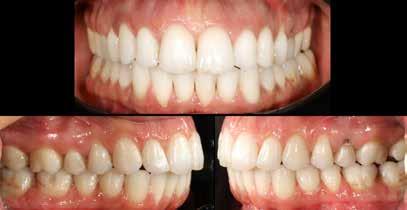

Hölgy páciensem az első konzultáció során tipikus kórtörténetet vázolt fel: Gyermekkora óta szeretett volna fogszabályozó készüléket, hiszen mindig is zavarta a class 2-es eltérésnél tipikusan jellemző nagy overjet (1-3. képek), és természetesen az ezáltal kifelé álló felső metszőfogai, részben a felső metszők protrúziója, részben pedig a disztálisan elhelyezkedő mandibula miatt. Annak ellenére, hogy több fogszabályozó szakorvosnál is járt az évek során, de mivel saggitális eltérése és az alsó metszőfogak torlódása miatt négy kisőrlőfog extrakcióját, illetve emellett sokszor állcsont műtétet is javasoltak neki, nem vágott bele a kezelésbe (4-5. képek).

A fogorvosa – nagyon helyesen – felhívta a figyelmét, hogy parodontális státusza is valószínűsíthetően romlani fog az eltérése miatt, újabb kört futott, immár 39 évesen, de még mindig premoláris fogak húzása és állcsontműtét nélkül szerette volna a fogszabályozást.

A konzultáció során arról is beszéltünk – ahogy az ilyenkor lenni szokott –, sohasem szeretett igazán mosolyogni, de a Pitts Protokolloknak köszönhetően az arc- és mosolyesztétikai céloknak megfelelően kerül megvalósításra az okklúziós korrekció. Az okklúziós kezelési célok az alábbiak voltak: a felső és alsó fogív nivellálása és tágítása, az alsó fogsor/ mandibula mezializálása, valamint a harapás megemelése által a mélyharapás rendezése.

A fogkontúrálás és az interproximális redukció alkalmazásával a mikroesztétikai részletek tökéletesítése is megtörtént (11. kép) A kezelés mindössze 16 hónapig tartott, megtörtént a rágófunkció helyreállítása, és az esztétikai végeredmény sokéves várakozás után valóban fordulópontot jelentett páciensünk életében (12-14. képek).